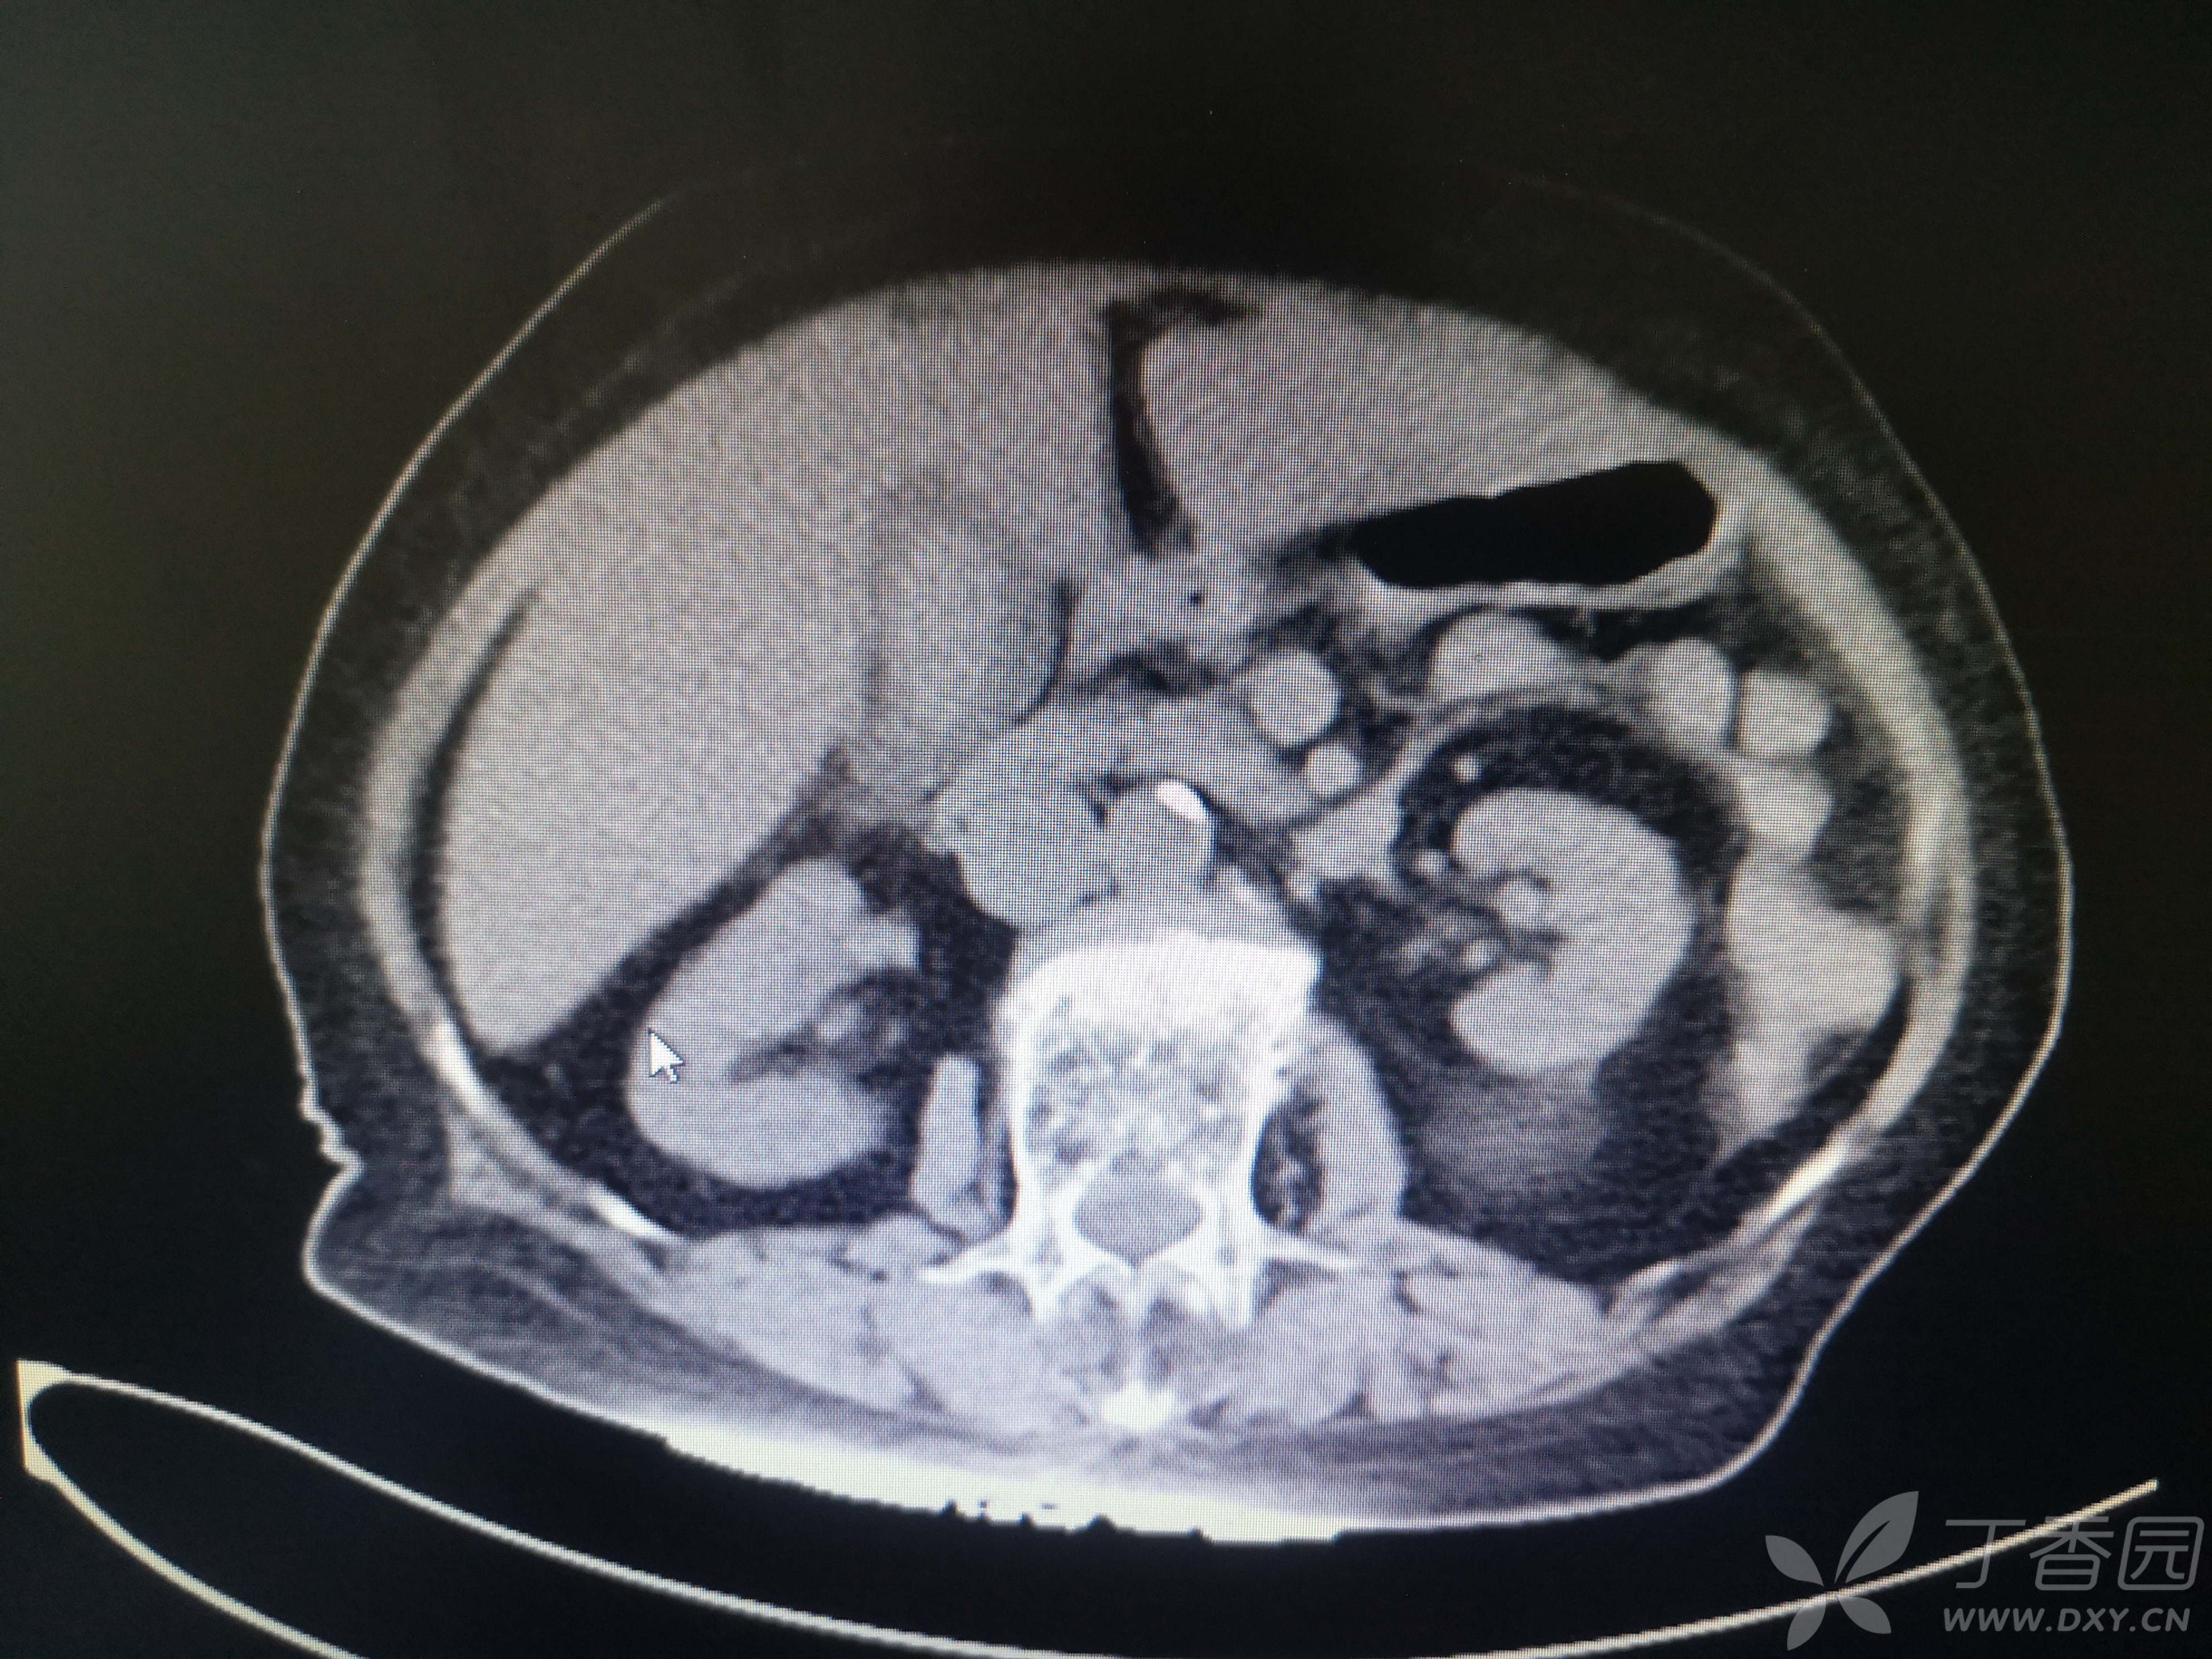

11小时前无明显诱因出现右腹部疼痛,伴恶心、呕吐,呕吐物清稀黏液,急至我院就诊,患者在家属搀扶下步入急诊室,神志清,言语费力,呼吸浅快,口唇、手足皮肤青紫,心电图示快速房颤,血压低至68/48mmHg,脉氧测不出,动脉血气分析PH 7.1,PCO2 13.6mmHg,PO2 135mmHg,Lac15.1mmol/L,HCO3 4.1mmol/L,K 6.11mmol/L。CT、血常规、血凝、生化等结果见图 。

患者CT图像如下

完善CT检查以后收入重症医学科治疗。